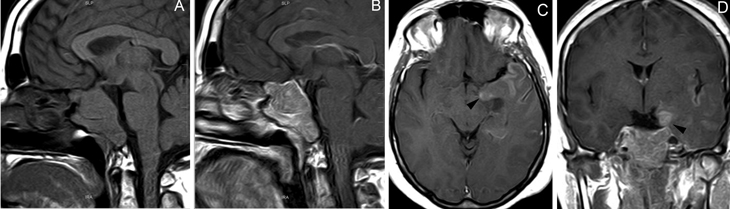

Figura 10A y B. Microadenoma pituitario (prolactinoma), secuencias T1W antes y después de contraste, cortes coronales. Sin Gadolinio el tumor tiene señal similar a la glándula pituitaria. La secuencia T1W post Gadolinio, muestra la glándula contrastada y a izquierda un tumor no contrastado, (hipointenso) de 7 mm (punta de flecha). Características de la imagen del adenoma pituitario

En el caso de los microadenomas, al ser tumores funcionantes, el cuadro clínico y de laboratorio ayuda a definir la localización de la lesión. La glándula pituitaria, considerando el pequeño tamaño de los tumores, puede mostrar forma y volumen normal. En un 20-25% de los casos no se logra demostrar los microadenomas menores de 3 mm, lo que aumenta al 40% en el casos de los adenomas productores de ACTH, en que los exámenes falsos negativos son más frecuentes36-38 (Figuras 11A, 11B, 11C y11D). En este grupo de pacientes es fundamental la utilización de protocolos de examen que incluyan cortes finos coronales de 1 mm en secuencias ponderadas en T1 antes, durante y después de la inyección de Gadolinio, para asegurar la detección de los adenomas, los cuales se contrastan en general más tardíamente que la glándula normal39-41 (Figuras 12A y 12B).

Figura 11A. Microadenoma pituitario productor de ACTH, corte coronal, secuencia T1w, muestra señal homogénea en la hipófisis. B. corte coronal (secuencia dinámica T1w con Gadolinio); se observa nódulo hipointenso de 3 mm (que aun no se refuerza) en cuadrante inferolateral izquierdo de la hipófisis (punta de flecha). C. corte coronal, secuencia tardía T1w con Gadolinio, muestra refuerzo heterogéneo de la glándula, no es posible precisar la ubicación del tumor. D. corte coronal, secuencia volumétrica SPGR T1w con Gadolinio de 1 mm de espesor, que muestra claramente la ubicación del tumor (punta de flecha). Esta secuencia ha mostrado mejores resultados en la evaluación de la enfermedad de Cushing.